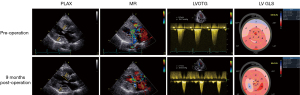

Guided by TEE, all surgeries were successfully performed, resulting in immediate hemodynamic improvements (Figure 2). None of the patients required blood transfusion, and no major complications or adverse events—such as permanent complete heart block, iatrogenic ventricular septal perforation, valvular injury, or cerebrovascular events—were observed. The postoperative course was uneventful, with all patients discharged in stable condition on postoperative day 7.

Mean septal thickness decreased from 26.0±4.1 mm preoperatively to 18.0±3.9 mm. Maximal instantaneous LVOT gradients were significantly reduced, from 111.0±44.3 mmHg preoperatively to 26.5±8.3 mmHg postoperatively, demonstrating effective relief of LVOT obstruction. All patients with preexisting MR (≥3+) and systolic SAM (≥2) exhibited notable improvements, with MR grade reduced to ≤2+ and SAM grade reduced to ≤1. Left ventricular GLS improved slightly from 6.6%±3.0% to 9.5%±2.3% (absolute values) on postoperative assessments (Figure 4). Additionally, left ventricular stroke volume, as a surrogate for myocardial contractility, improved significantly in all patients.

All patients presented extremely impaired left ventricular GLS before surgery, particularly in the basal inferolateral segments, corresponding to regions of LGE on CMR. Chang et al. demonstrated that impaired GLS was predictive of major adverse cardiovascular events and may enhance prognostic assessment in patients with severe Fabry-related LVH (17). Therefore, the postoperative improvement in GLS following TA-BSM may indicate a potentially better long-term prognosis. Although some patients showed reduced right ventricular free wall longitudinal strain, its independent prognostic significance remains unclear (18).